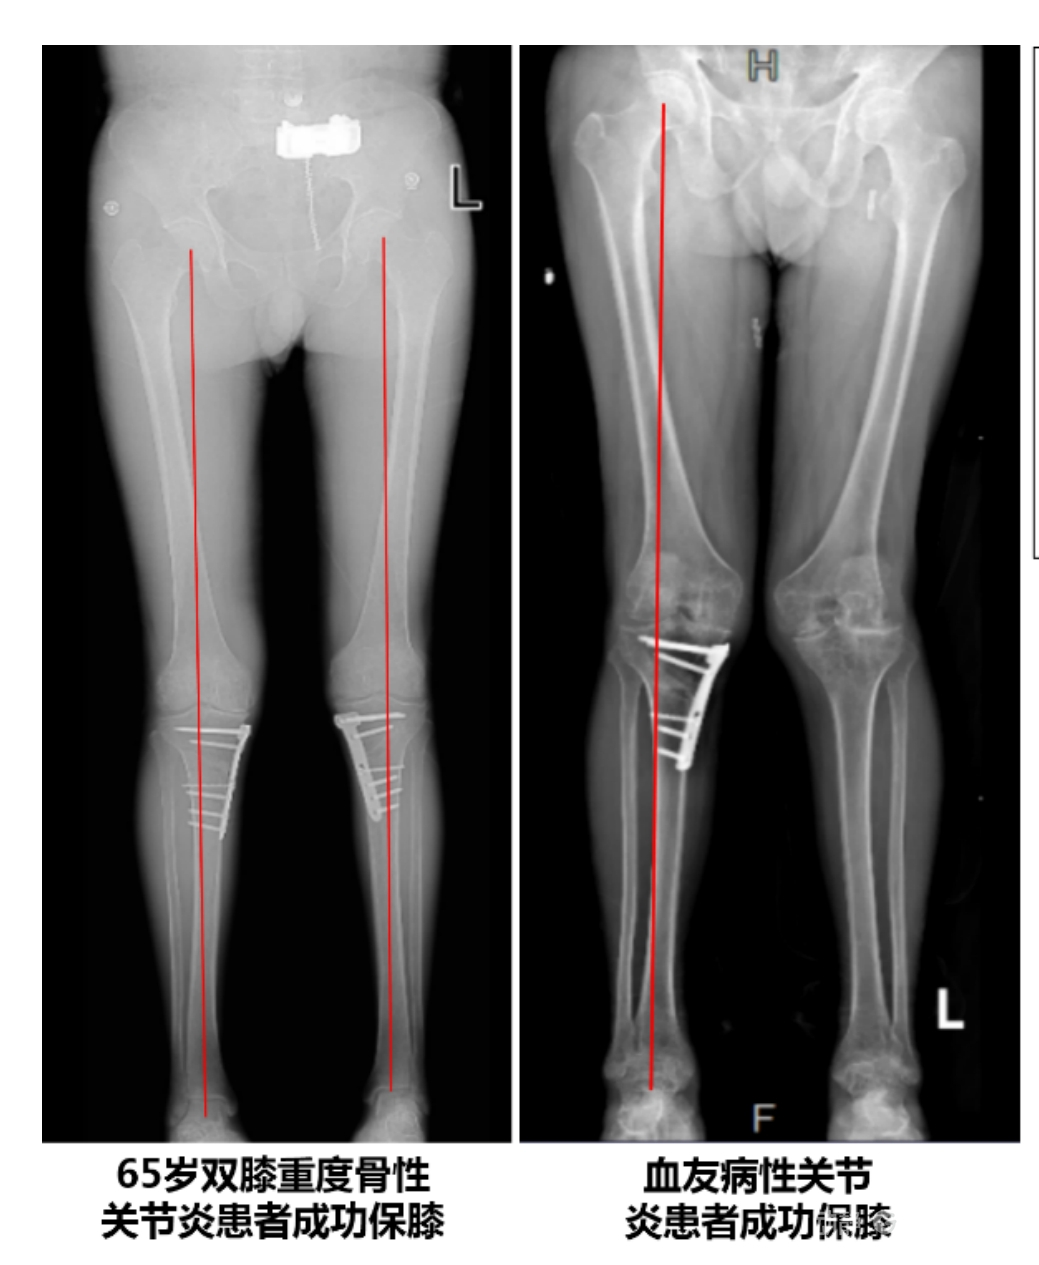

4.2 APTT-HTO脛骨高位截骨術(shù)

2025年7月,貴州醫(yī)科大學(xué)附屬醫(yī)院骨科團(tuán)隊(duì)原創(chuàng)研發(fā)的腘肌前結(jié)節(jié)中脛骨高位截骨保膝術(shù)(Anterior Popliteus Transtibial Tuberosity-High Tibial Osteotomy, APTT-HTO)及其提出的脛骨結(jié)節(jié)分區(qū)與腘肌保護(hù)理論,登上了國(guó)際頂尖學(xué)術(shù)舞臺(tái)。該成果在全球最具影響力的專業(yè)會(huì)議之一——日本骨科協(xié)會(huì)第98屆年會(huì)上進(jìn)行了兩次學(xué)術(shù)發(fā)言。[8]

該手術(shù)具有經(jīng)皮微創(chuàng)、保留原生膝關(guān)節(jié)結(jié)構(gòu)、符合階梯治療原則等優(yōu)勢(shì),通過調(diào)整下肢力線可促進(jìn)部分軟骨再生,術(shù)后關(guān)節(jié)功能接近正常(如下蹲、爬山),患者還能從事中重體力勞動(dòng)。相比其他術(shù)式,其有效規(guī)避了髕骨低位、血管損傷、合頁骨折等潛在并發(fā)癥。

目前,APTT-HTO技術(shù)已成功應(yīng)用于千余名患者,幫助保留自身膝關(guān)節(jié)。此類保膝手術(shù)適用于單間室膝關(guān)節(jié)炎患者(如 “羅圈腿”),核心是通過調(diào)整力線糾正畸形,減輕磨損間室壓力、發(fā)揮健康間室作用,延長(zhǎng)膝關(guān)節(jié)壽命。若出現(xiàn)膝關(guān)節(jié)疼痛、保守治療無效且X線顯示關(guān)節(jié)間隙部分狹窄,建議及時(shí)就醫(yī)評(píng)估是否適合手術(shù)。